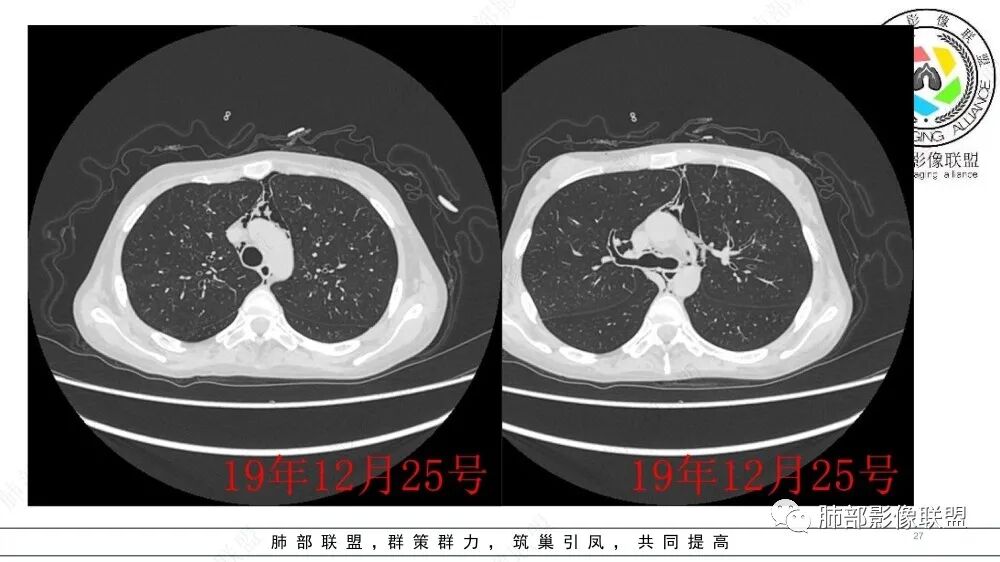

青年女性,干细胞移植后出现憋喘胸闷气短,术前和术后CT可见支气管进行性扩张,双肺野淡磨玻璃影,考虑移植后抗宿主病,闭塞性细支气管炎(BO)。

干细胞移植后,肺CT较前比较两肺支气管轻度扩张,管壁增厚,两肺透亮度增高,纵膈气肿,考虑闭塞性细支气管炎

这个主要是临床,影像比较单一,有纵隔气肿;两侧对比:后者确实肺密度减低,体积增大,有气体潴留的特点